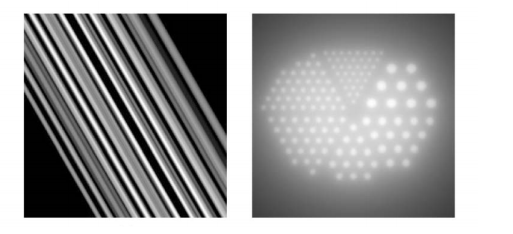

What causes Aliasing artifact and noise?

Aliasing artifact and noise * Insufficiency of data * Under sampling projection data * Not enough projections * Under sampled grid for display * Presence of random noise in the measurements

When does Aliasing errors in projection data occur?

Aliasing errors in projection data occur * N (sample of projections) is small and K (number of projections) is large * Choose sample interval \tau * The corresponding band width is W=1/2\tau * Further assume W \< B * Linearity holds so the images can be analyzed as a sum of: * The image made from the bandlimited projections * The image made from the aliased portion of the spectrum * Subtracting the two reconstructions =\> The streaks are gone

32

What happens during Insufficient number of projections?

Insufficient number of projections * N (samples of projections) is large and K (number of projections) is small * A small number of filtered projections of a small object that are backprojected will result is a star shaped pattern * The number of projections should be roughly equal to the number of rays in each projection